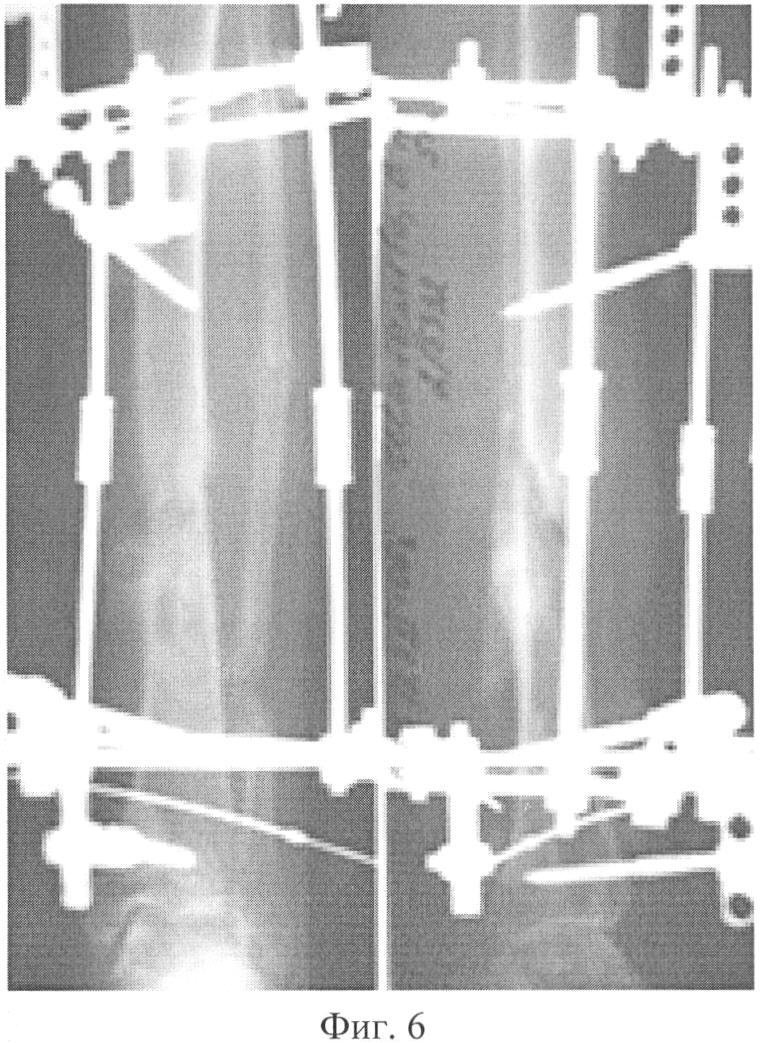

Фиг.6. Фотографии и фоторентгенограммы больной Ш. перед снятием АВФ;

Больная Ш., 52 лет, поступила на 2 отд. РНИИТО 18.05.2006 с диагнозом: Ложный сустав средней трети левой большеберцовой кости. Рентгенологически отмечалась антекурвационная деформация с углом 24 град. и варусная деформация с углом 27 град. (Фиг.3). 24.05.2006 выполнена операция: Остеотомия левой малоберцовой кости в н/3, наложение аппарата Соломина-Утехина-Виленского (Фиг.4). С 29.05.2006 начато устранение деформации. Деформация устранена за 12 суток (Фиг.5). После устранения деформации система из 6-ти телескопических штанг заменена на штанги из набора аппарата Илизарова. Перелом сросся (Фиг.6). Период фиксации составил 130 дней; аппарат демонтирован (Фиг.7).